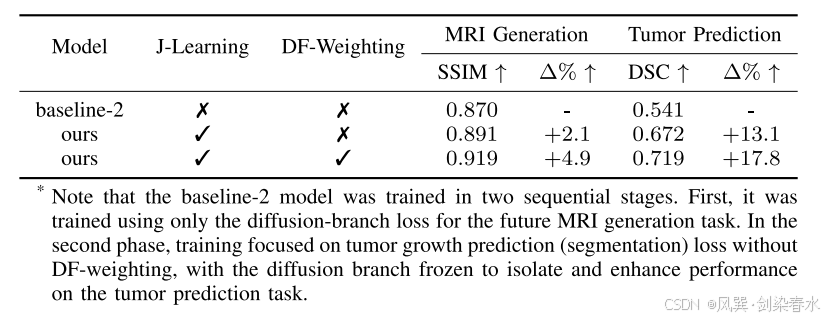

Table 5 | 联合任务学习机制的影响:(消融实验)